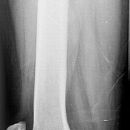

Distaler Oberschenkel a.-p (1. Ebene)

Fraktur, Z. n. Osteosynthesematerial

Rückenlage

aufzunehmendes Bein gestreckt

Bein gestreckt und leicht nach innenrotiert, sodass die Epicondylen auf einer Höhe sind (Patella mittelständig)

ZS senkrecht auf Objekt und auf Detektormitte

Länge voll, unteres Licht 2 QF unterhalb der Patella, lateral Hautgrenze

Bei distaler Aufnahme muss das Kniegelenk orthograd getroffen werden.